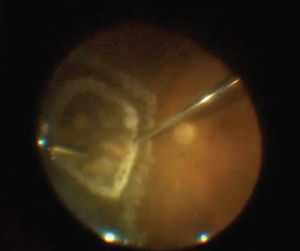

| Figure 4. The sclerotomy has been enlarged, cannula removed and infusion line pinched, and the filter paper held by the assistant is ready to receive the specimen as it is removed from the eye (A). Then the intact retino-choroidal section is flattened and spread on the filter paper (B). |

That said, as your last step before removing the specimen, pinch your infusion to prevent excessive turbulence. Finally, have filter paper and an assistant ready to “catch” the specimen as you remove it from the eye (Figure 4, page 23). Usually the specimen can be removed en-bloc, but sometimes the retina and RPE/choroid come out in separate layers.

| Figure 5. At six months postoperatively, extensive laser barricade is still evident. This patient had some residual hemorrhaging immediately after the biopsy, but it resolved. |